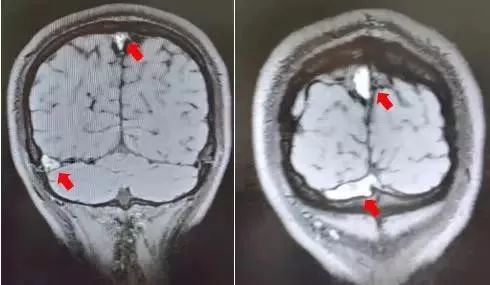

磁共振黑血成像显示小王的上矢状窦、横窦及乙状窦多处血栓形成(红色箭头处)